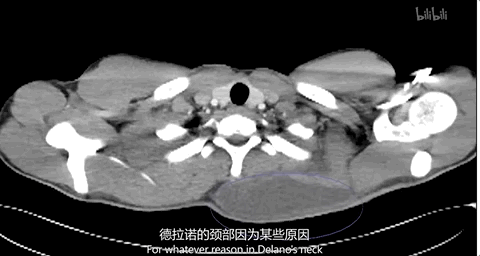

通过断层扫描,李医生发现问题出在淋巴:

“人体内的淋巴系统,本质是管道系统,如果将它比作花园水管,小伙子的颈部淋巴管就像是水管堵住或打结,水都堵在了后面。”

抽积液治标不治本,需要外科手术疏通淋巴。